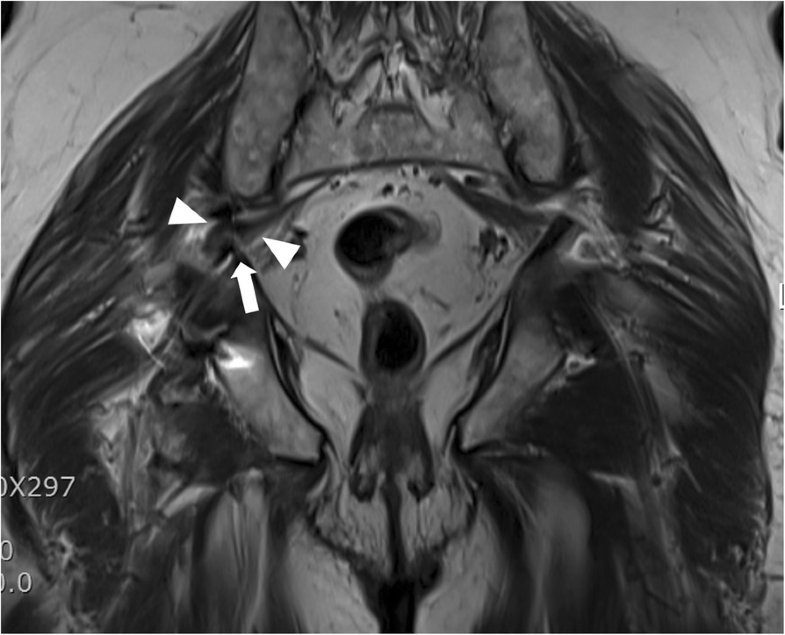

Endoscopic resection of acetabular screw tip to sciatic Endoscopic Decompression Of Sciatic Nerve The evaluation of posterior hip pain. We describe an effective endoscopic technique for piriformis tenotomy and sciatic nerve neurolysis. The purpose of this study is to assess the effectiveness of endoscopic sciatic nerve decompression and evaluated the differences of. Patients were treated with sciatic nerve decompression by resection of fibrovascular scar bands, piriformis tendon release, obturator internus, or quadratus femoris. Endoscopic Decompression Of Sciatic Nerve.